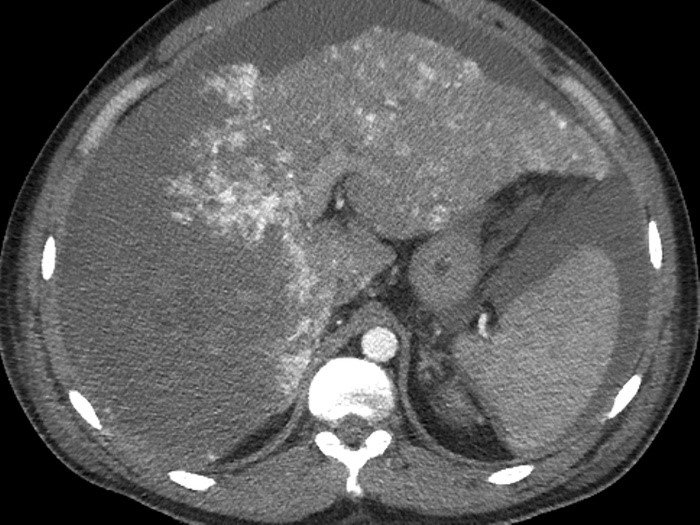

- Diaqnozu dəqiqləşdirmək üçün Qc venaları yoxlanılmalıdır. Bunun üçün dopler USM, KT-angioqrafiya, MRT-angioqrafiyalar və ya kontrastlı venoqrafiya edilir.

- Görüntüləmədə Qc venalarının trombotik tutulması diaqnozu dəqiqləşdirən əlamətdir.

PVT diaqnozunu dəqiqləşdirmək üçün portoqrafiya aparılır – Doppler USM, KT və ya MRT angioqrafiya.

- Kontrastlı müayinələrdə damarda tromb və ya kavernoz transformasiya

Baddi-Kiari sindromu böyük qaraciyər venalarının tıxanması nəticəsində meydana gələn venoz durğunluqdur, qaraciyər venaları ilə yanaşı aşağı boş venada da tıxanma ola bilir. Tromboz, fibroz, membran və infiltrasiya (şişlər, iltihab) ən çox rast gələn səbəbləridr. Erkən mərhələlərdə kəskin hepatit və kəskin qaraciyər yetməzliyi, xroniki mərhələdə sirroz və PH meydana gələ bilir. Diaqnozu üçün tomoqrafiya və kontrastlı angioqrafiya lazım gəlir, Qc venalarının trombotik tutulması diaqnozu təsdiqləyir. digər xarakterik əlaməti birinci seqmentin hipertrofiyasıdır. Erkən mərhələdə dekompressiya (cərrahi və stend) sirroz əmələ gəldikdə isə transplantasiya ön planda tutulur.

Qaraciyər venalarının görünməməsi, kontrastlaşmaması və ya trombla tıxanması.

- portoqrafiyada vena mənfəzində trombun görünməsi;

- venanın distalında genişlənmə və kavernoz transformasiyanın görünməsi;